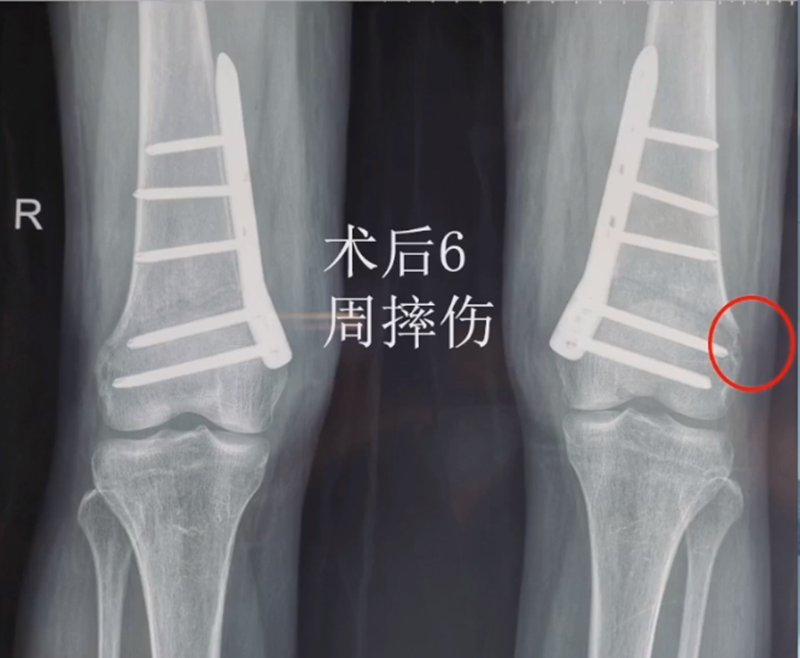

术后6周摔伤,一侧出现膝内翻。

影像学检查显示左侧出现合页断裂。